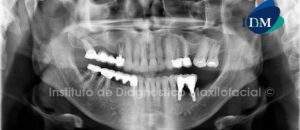

Paciente masculino 72 años de edad es referido al Instituto de Diagnóstico Maxilofacial para la colocación de un implante dentario a nivel de la pieza 4.6.